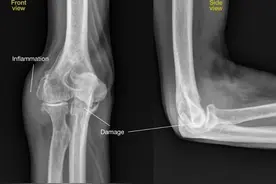

我们很多人都认为骨关节炎可能发生在膝关节、髋关节或者是手指比较多,但是确实有一部分人会发生在肘关节,而且一旦发生在肘关节问题还比较严重,因为肘关节骨关节炎会导致肘关节的骨质增生,关节会发生变形,会严重影响肘关节的旋转以及屈伸功能,而且在肘关节内侧有一个非常重要的神经,叫做尺神经,